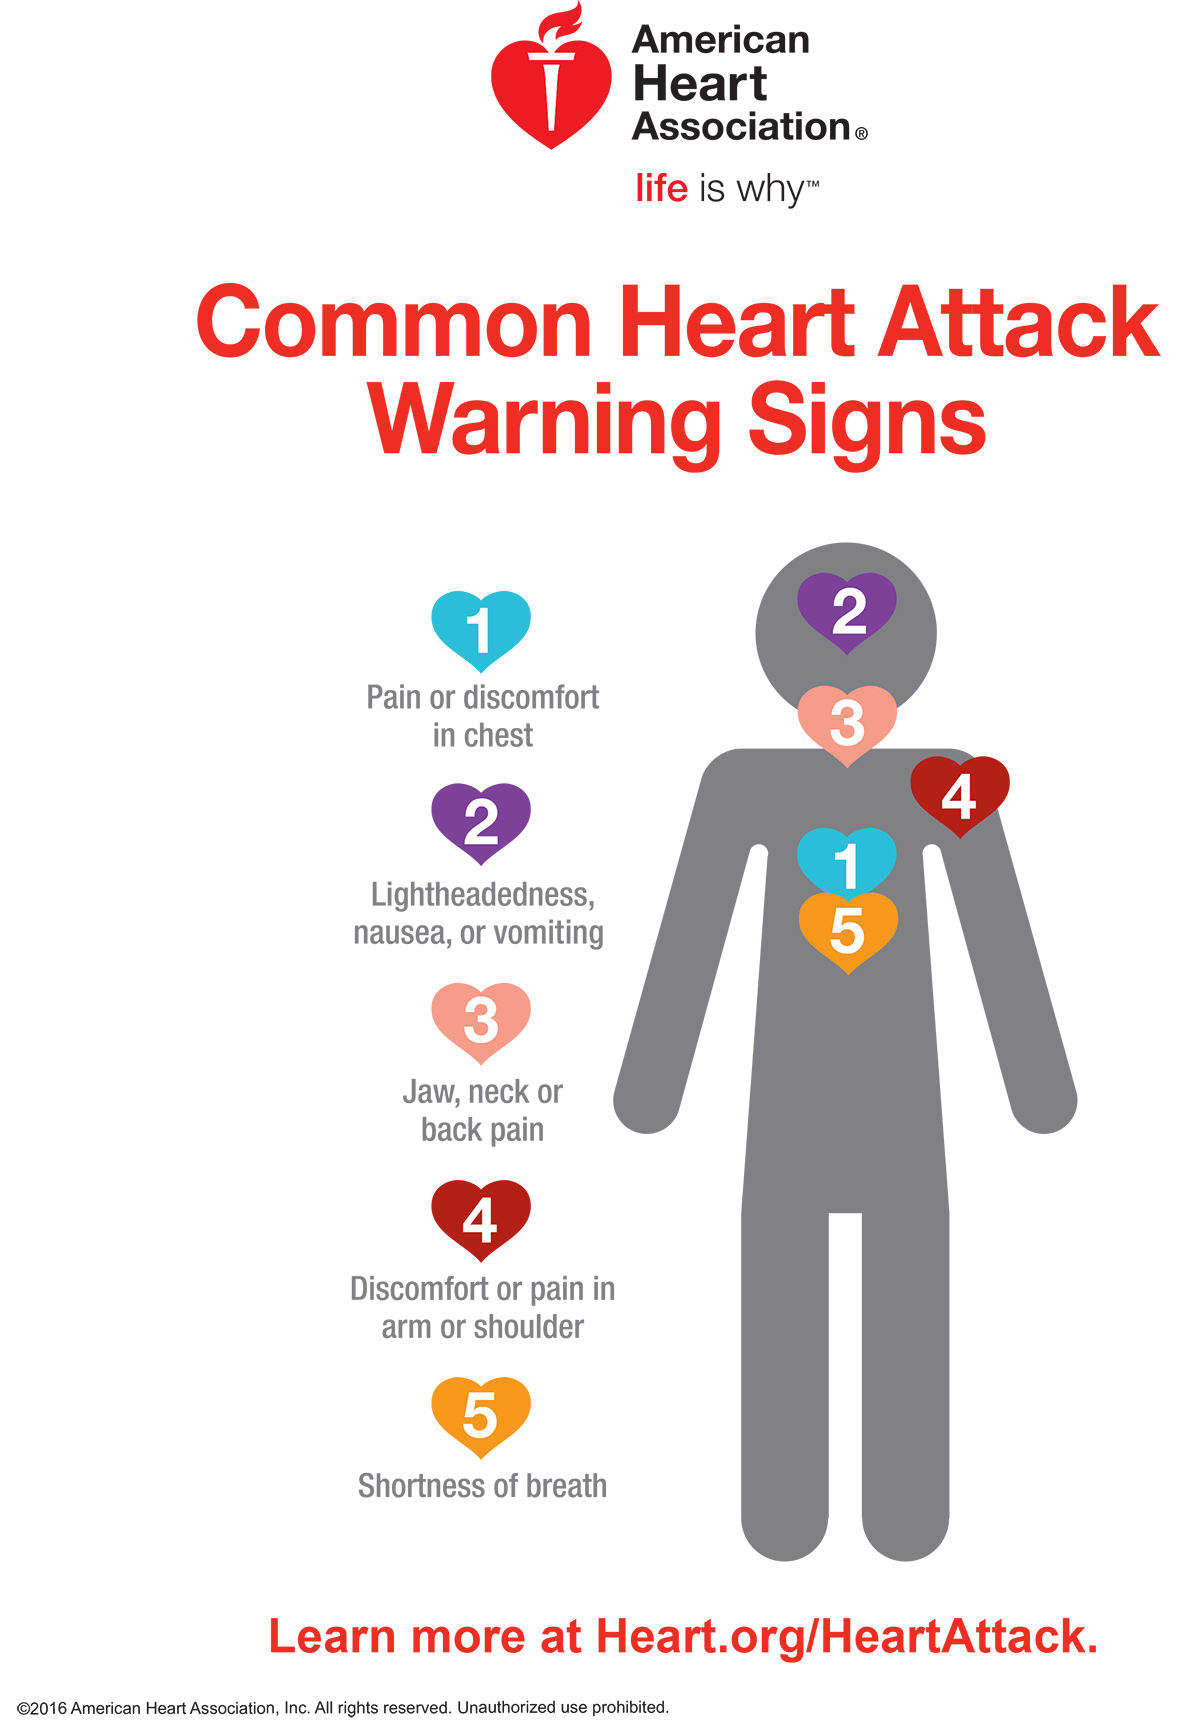

What Medication To Give During Heart Attack

What Medication To Give During Heart Attack

It Is Common Knowledge That The Symptoms Of Heart Attack Can Be

APEX Heart Centre Patient Information

https://apexheartcentre.com/wp-content/uploads/2021/07/ACC-heart-attack-infographic_page1-794x1024.png

Heart Attack Poster First Aid Oz

Heart Attack Poster First Aid Oz